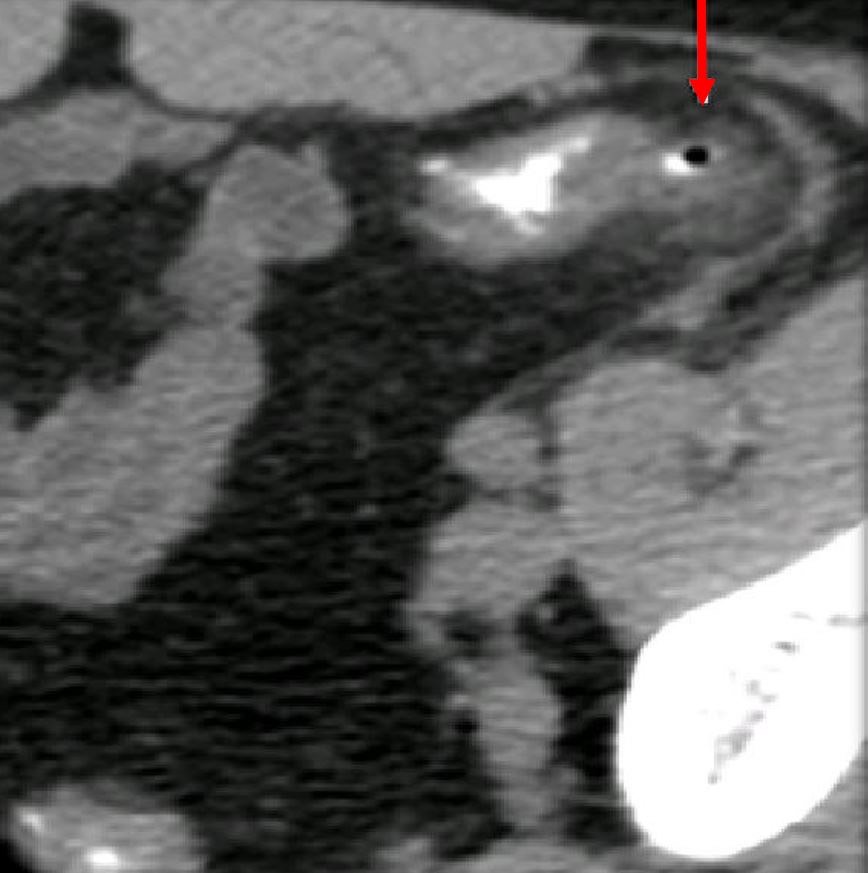

951. На представленном КТ снимке фрагмент сигмовидной кишки; визуализируется дивертикул с утолщенными стенками и локальной инфильтрацией вокруг, что по классификации осложнений дивертикулярной болезни соответствует картине